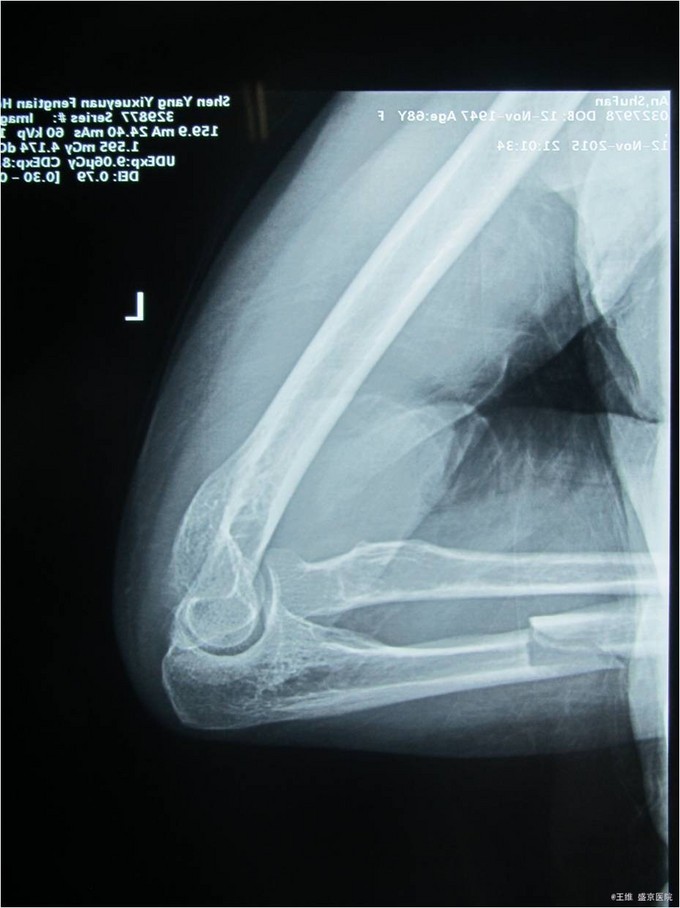

患者自诉于2015年11月12日晚6点左右走路时被汽车撞到,左前臂着地,当时左前臂疼痛,不能活动。急诊去沈阳市八院就诊,并拍片示左尺骨骨折骨折,患者及家属为求进一步手术治疗而来我院,急诊以“左尺骨干骨折”为主要诊断收入我科.病来患者饮食二便正常。

专科查体:左前臂中段肿胀,未见明显畸形,压痛(+),叩击痛(+),左肘关节及腕关节活动度良好,左手各手指活动度良好,感觉正常